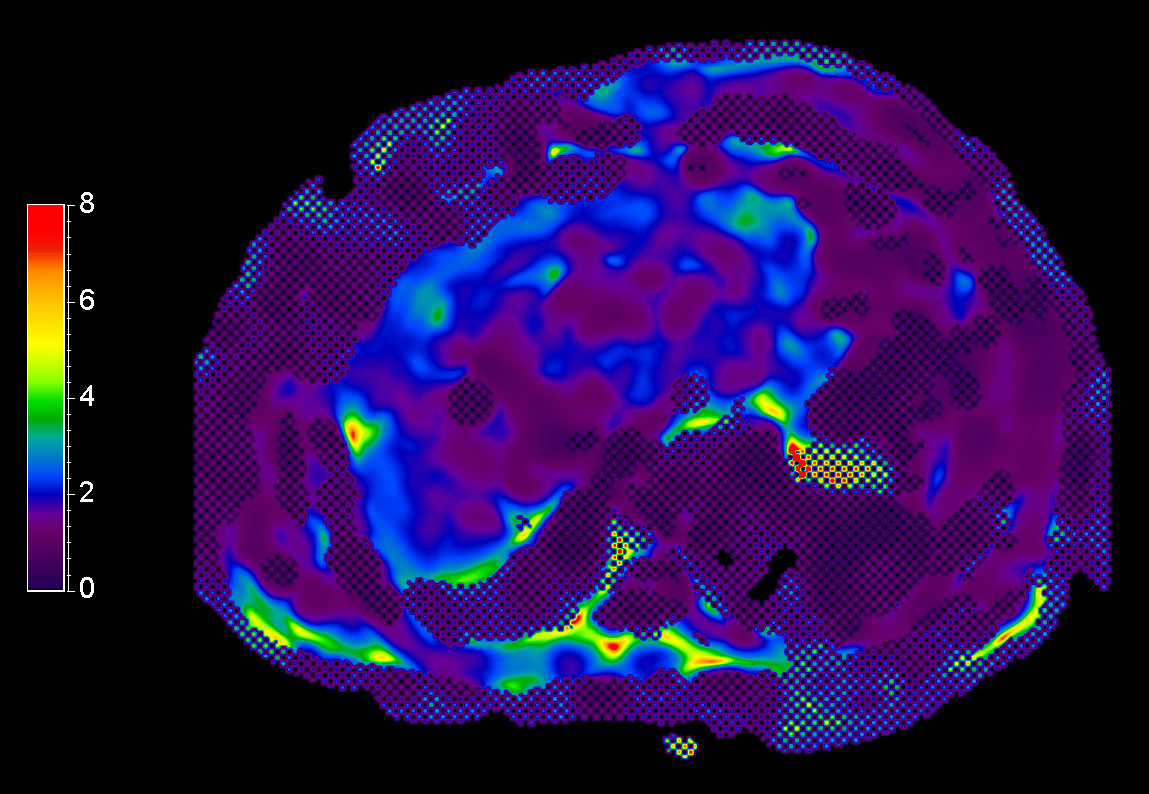

MR Elastography (stiffness map) SE-EPI, 13 sec BH/4 slices

MR Elastography (stiffness map) SE-EPI, 14 sec BH/8 slices